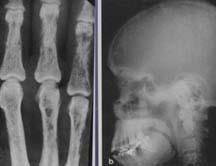

骨X線檢查

骨X線檢查使診斷腎性骨病的經典方法之一。骨骼X線檢查可以發現繼發性甲旁亢所致的骨膜下吸收、骨質疏鬆、病理性骨折、佝僂病和骨軟化等,以及繼發性甲旁亢或β2微球蛋白澱粉樣變引起的骨囊性病變。但僅靠X線檢查不能明確腎性骨病的組織類型及骨轉運率,亦不利於骨病的早期診斷。